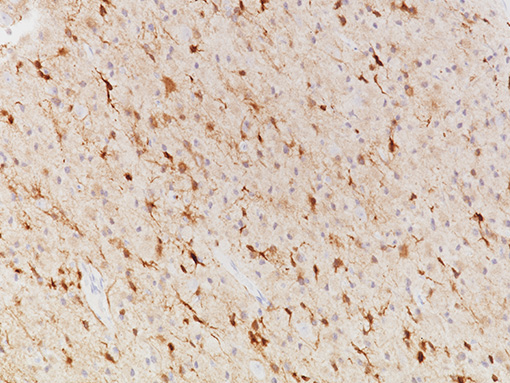

Isocitrate dehydrogenase 1 (IDH1) is an enzyme that catalyzes the oxidative decarboxylation of isocitrate to alpha-ketoglutarate, producing NADPH (1). However, abnormal IDH1 caused by somatic missense mutations may occur when substitution from arginine to histidine at codon 132 (IDH1 R132H) inhibits the wild-type IDH1 enzymatic activity, leading to production of 2-hydroxyglutarate, a possible oncometabolite. The accumulated oncometabolite promotes formation and malignant progression of gliomas (2). IDH1 R132H detection by immunohistochemistry can be used for the diagnostic differentiation between grade II/III gliomas, secondary glioblastomas and primary glioblastomas. The IDH1 R132H mutation correlates with a positive clinical outcome in patients with astrocytic tumors. Recently, studies indicated that IDH mutations along with ATRX status, and in combination with other classical biomarkers, helped refine the molecular classification of adult gliomas, providing a prognostic tool for clinicians (3). Data indicate that IDH1 R132H expression could be used as a predictive marker of prognosis for patients with gastrointestinal cancer (1).

| CLONE | IHC132 |

| POSITIVE CONTROL | Astrocytoma |